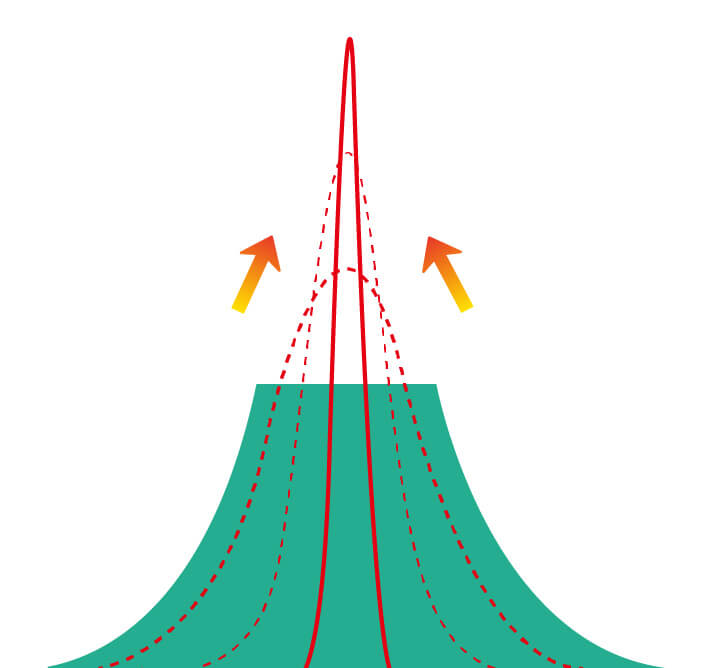

百老汇电子游戏官网新开发的内镜染色技术,主要是基于多波长LED 光源的开发,VLS-55Q 四波长LED 光源是由四个不同颜色的LED光按照相应照明模式所规定的特定发光比例进行合束后形成,合束后形成的照明光的光谱由红光、绿光、蓝光及蓝紫光这四个不同的波段范围构成。具有更高光谱自由度,通过光谱比例的控制,实现了聚谱成像技术,英文全称为“Spectral Focused Imaging, SFI”,缩写为“SFI”和光电复合染色成像技术,英文全称为“Versatile Intelligent Staining Technology, VIST”,缩写为“VIST”。